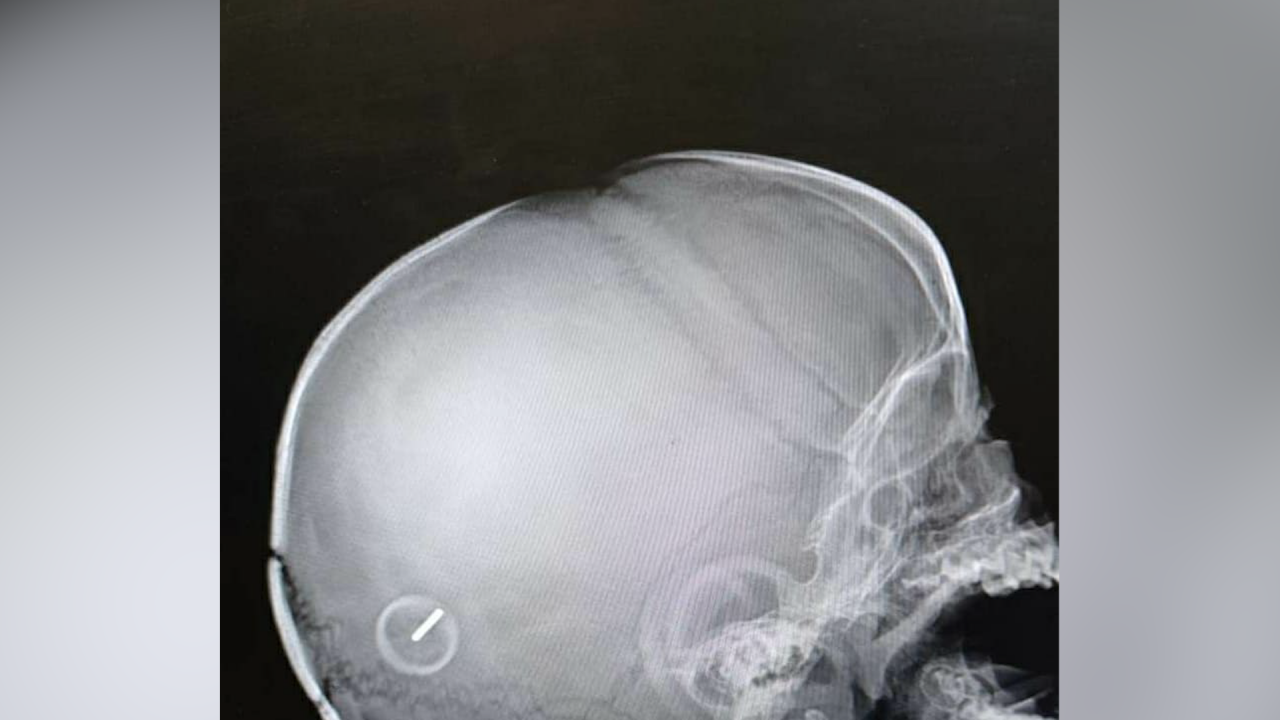

В Москве врачи спасли жизнь десятимесячной девочке, вытащив у неё из головы колёсико от игрушечной машинки. Штырь детали проткнул теменную область слева, рассказала пресс-служба Мосгорздрава. Девочку экстренно доставили в детскую больницу, после чего ею занялись профессионалы.

По словам родителей, девочка просто неудачно упала дома. Отмечается, что просто взять и вытащить предмет из головы малышки было нельзя. Так, чтобы детально оценить ситуацию, ей сначала сделали рентген, а затем с помощью ультразвука проверили, не повреждён ли мозг. Увидев, что всё в порядке, в операционной хирурги достали застрявшее колёсико специальным инструментом.

По окончании сложной операции крохе повторно сделали рентген, чтобы проверить, не остались ли в её голове какие-либо фрагменты машинки. Как стало известно, сейчас девочку уже выписали, она находится дома. У ребёнка осталось лишь небольшое отверстие в черепе, но оно никак не помешает нормальной жизни.